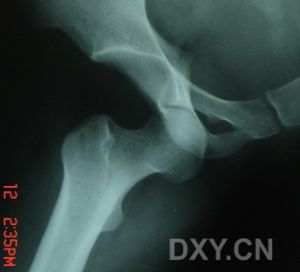

距骨骨折X片(2)、全面體檢:注意有無休克、軟組織傷、出血、檢查創口大小、形狀、深度及污染情況。有無骨端外露,有無神經、血管、顱腦、內臟損傷及其他部位的骨折。對嚴重傷員必須快速進行。

(3)、X線檢查:除正、側位X線攝片外,尚應根據傷情拍攝特殊體位相,如開口位(上頸椎損傷)、動力性側位(頸椎)、軸位(舟狀骨、跟骨等)和切線位(髕骨)等。複雜的骨盆骨折或疑有椎管內骨折者,尚應酌情行體層片或CT檢查。

(1)、有外傷史。(2)、上述症狀和體徵。如腫痛、壓痛、畸形等。(3)、X線攝片可見骨折。